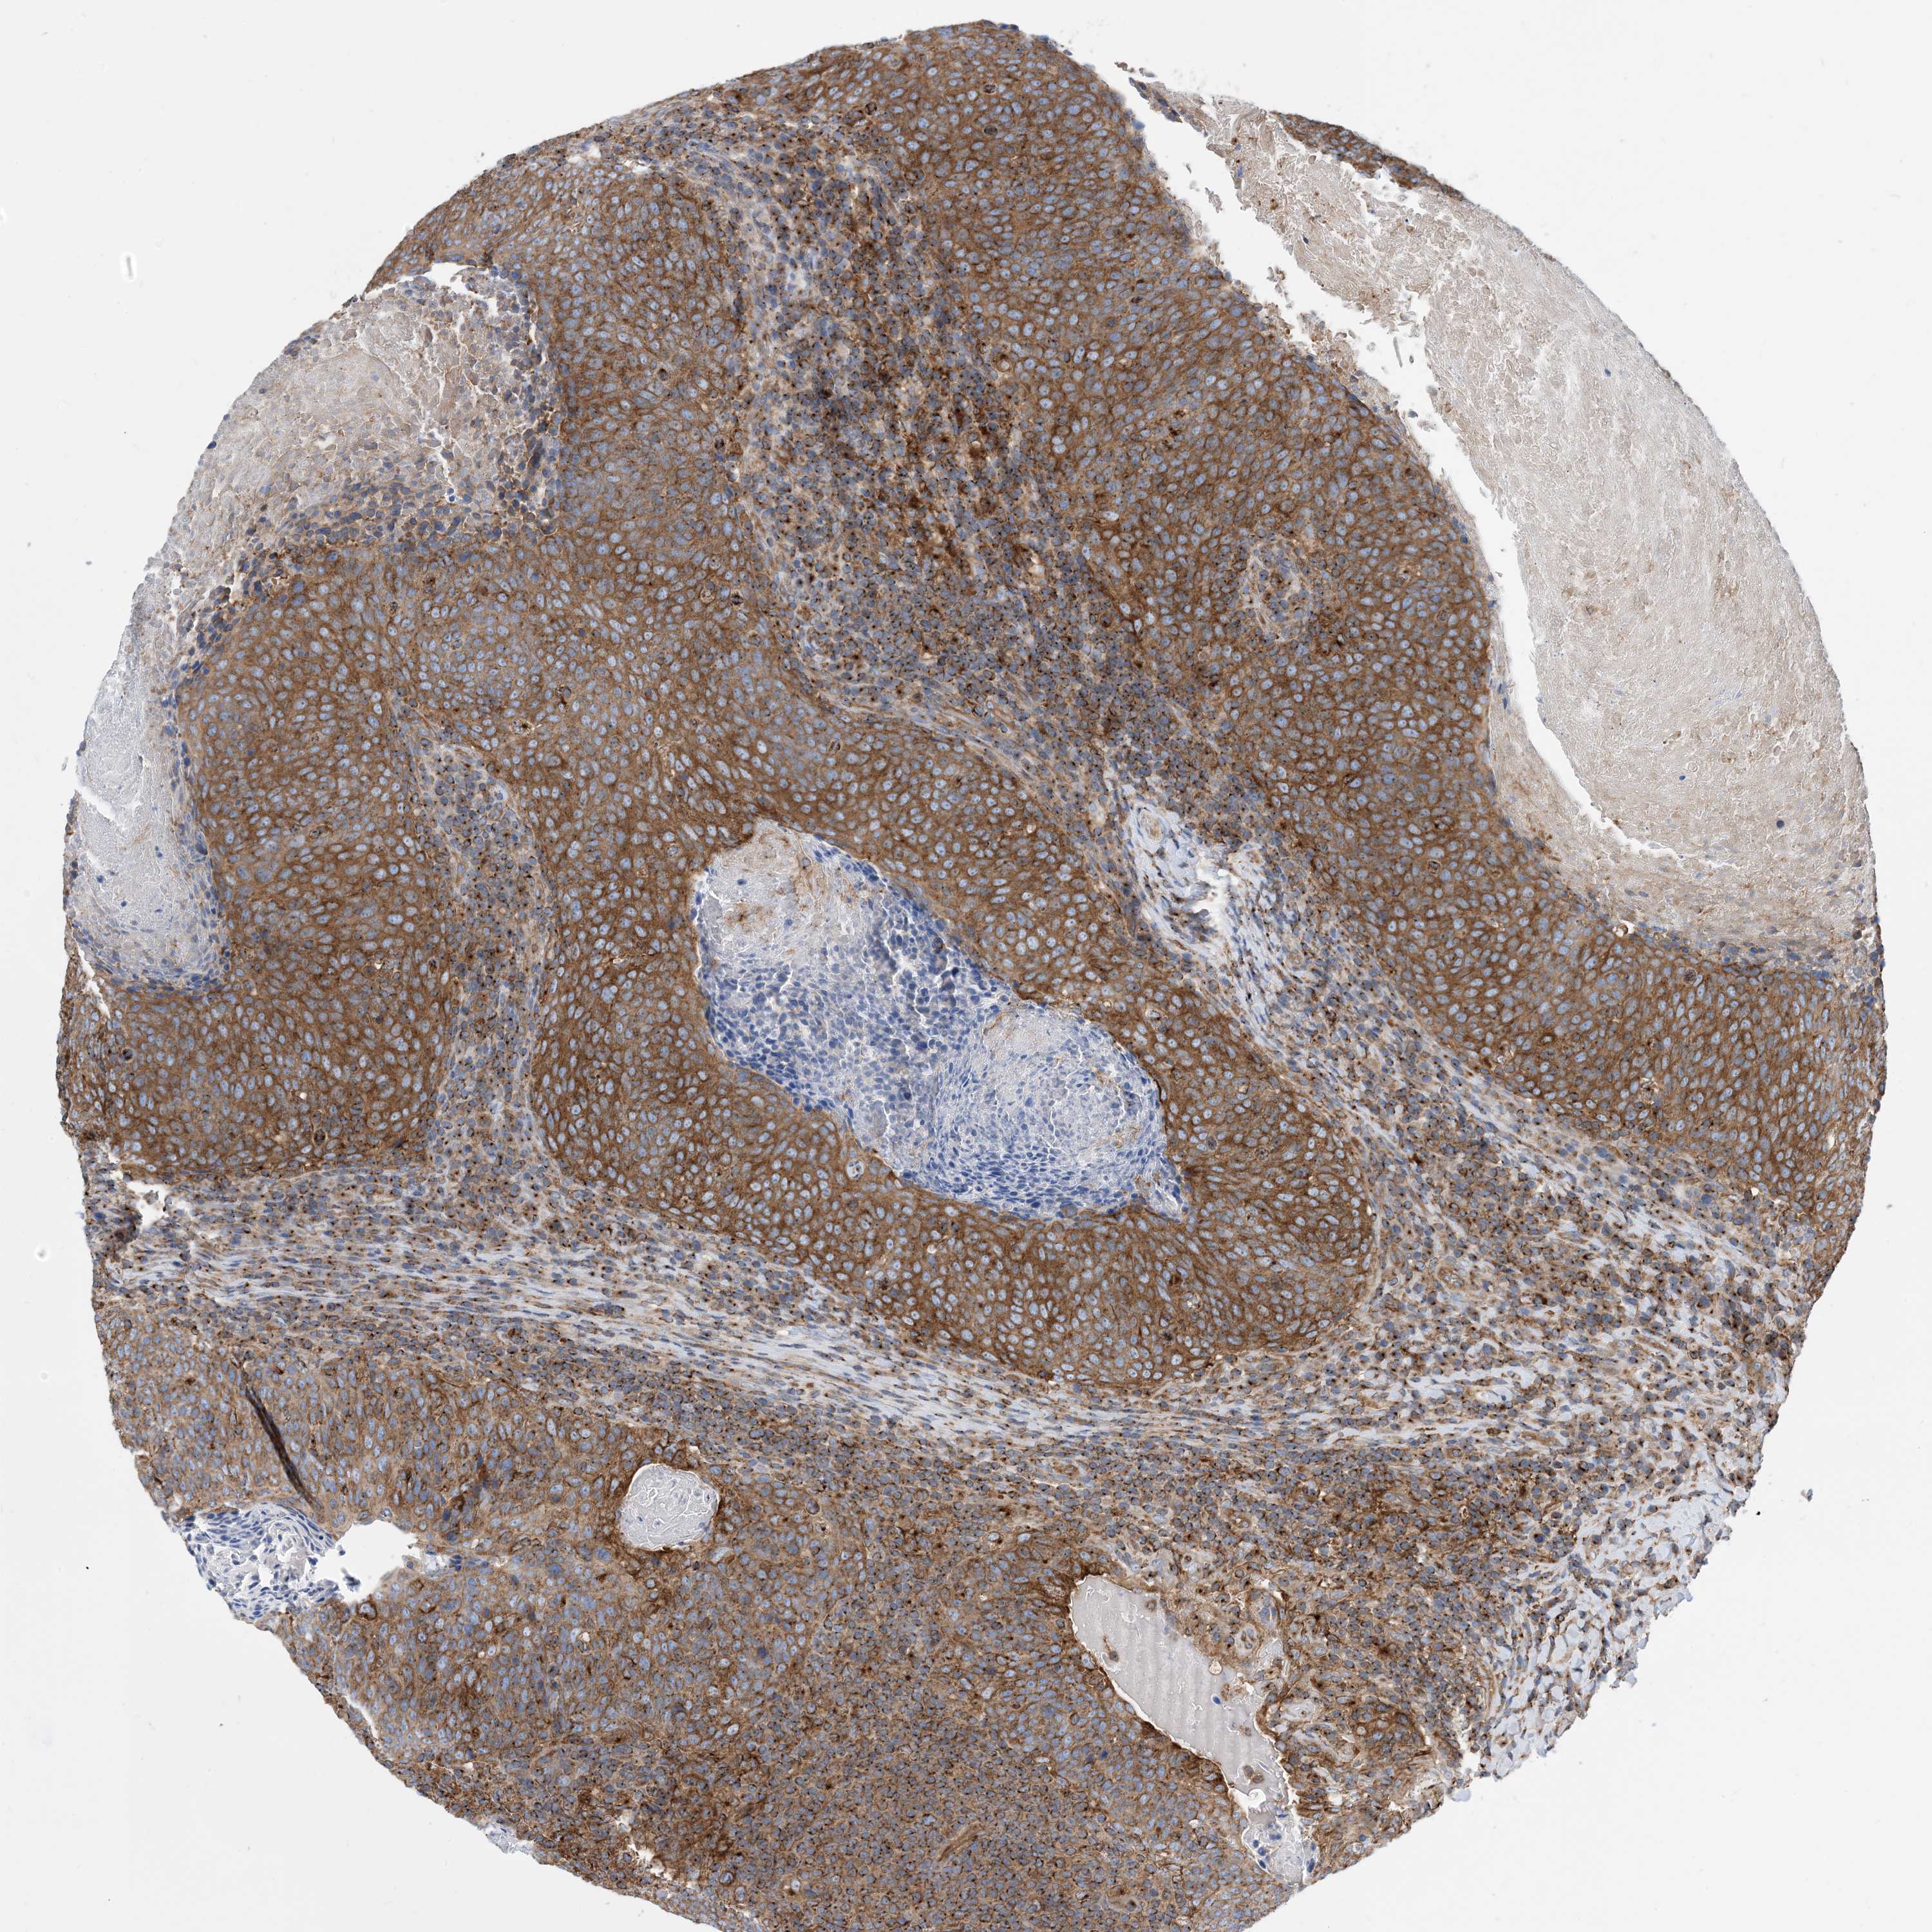

HEAD AND NECK CANCER - Protein expressioni

A mouse-over function shows sample information and annotation data. Click on an image to view it in a full screen mode. Samples can be filtered based on level of antibody staining by selecting one or several of the following categories: high, medium, low and not detected. The assay and annotation is described here.

Antibody stainingi

Antibody staining in the annotated cell types in the current human tissue is reported as not detected, low, medium, or high, based on conventional immunohistochemistry profiling in selected tissues. This score is based on the combination of the staining intensity and fraction of stained cells.

Each image is clickable and will lead to virtual microscopy that enables deeper exploration of all samples and also displays staining intensity scores, fraction scores and subcellular localization as well as patient and tissue information for each sample.

Antibody HPA035013

Staining

High

Medium

Low

Not detected

Intensity

Strong

Moderate

Weak

Negative

Quantity

>75%

75%-25%

<25%

None

Location

Nuclear

Cytoplasmic/membranous

Cytoplasmic/membranous,nuclear

Squamous cell carcinoma, NOS